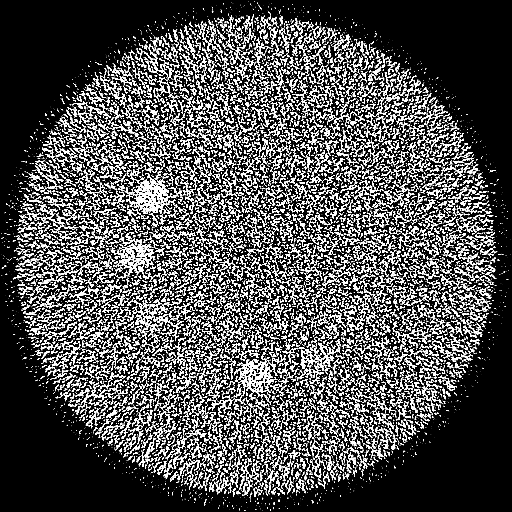

Reconstructed 35 – 85 keV Mono-Energetic Images

Deep Learning-based Mono-Energetic Images

(20-cm cylindrical phantom)

Iodine Maps Generated Using Mono-Energetic Images